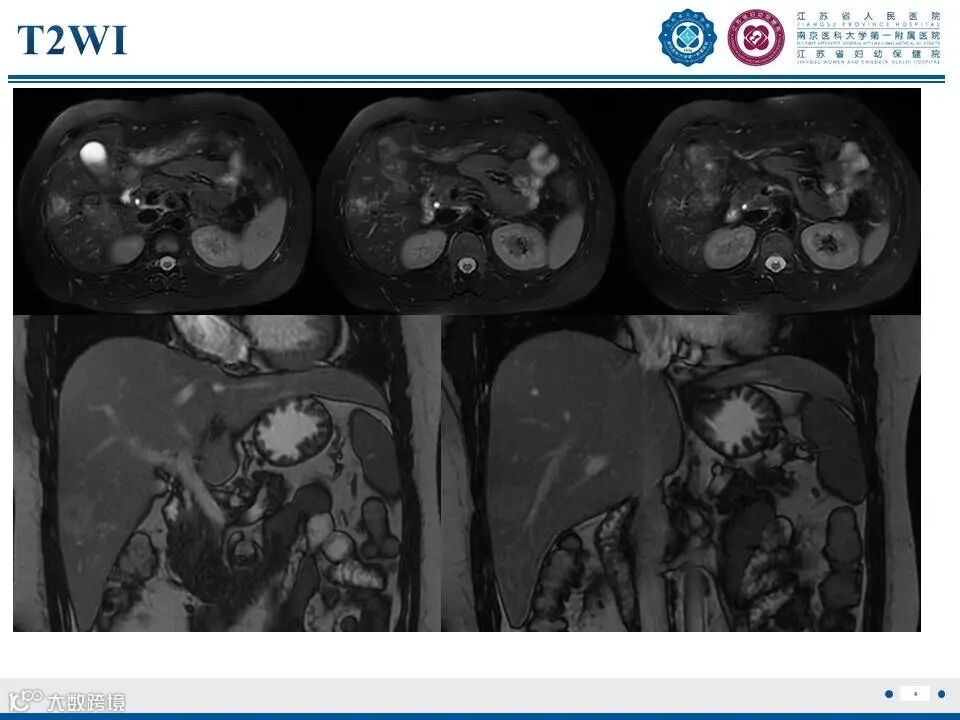

肝脏局灶性结节性增生——非典型瘢痕II影像诊断

肝脏局灶性结节性增生——非典型瘢痕II影像诊断 鼎湖影像